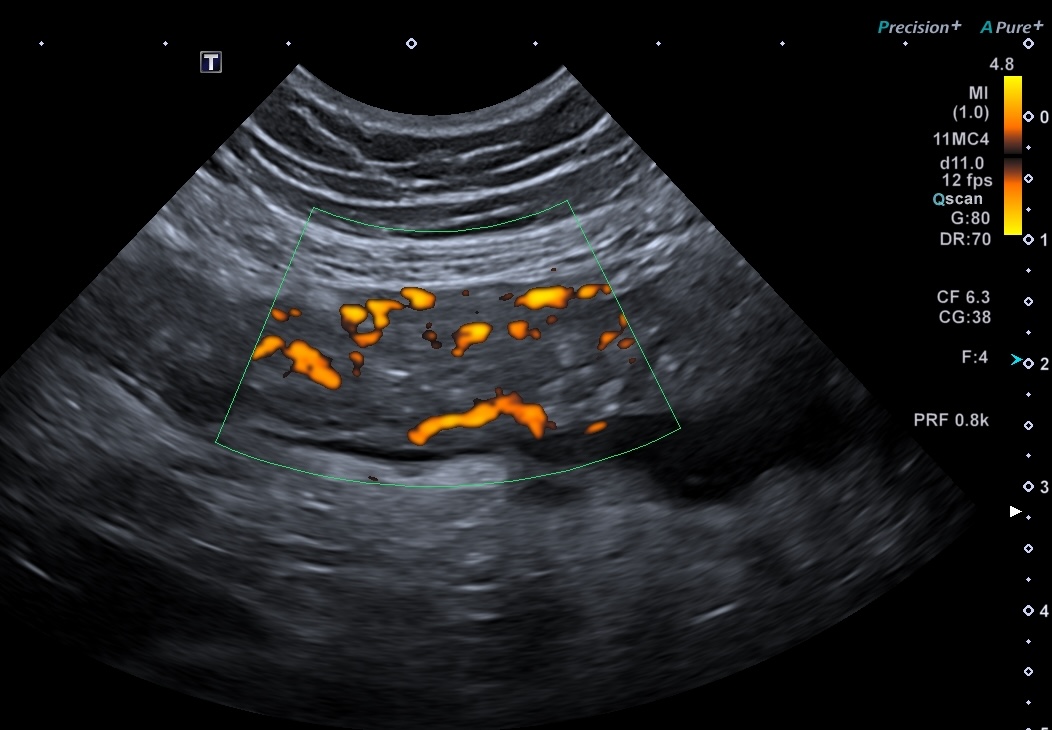

Activité Doppler intense de la paroi et de la graisse

Maladie de Crohn intense activité Doppler paroi et graisse